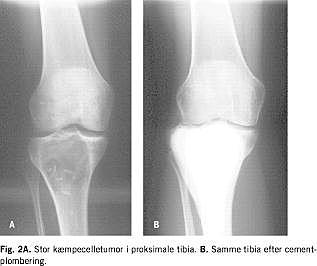

Alle patienter blev operativt behandlet. I begyndelsen af perioden blev der anvendt curretage eventuelt efterfulgt af opfyldning af kaviteten med autolog/heterolog knogle

Fig. 2A ). I de senere år har man efter curretage i stedet anvendt knoglecementering (Fig. 2B ). Såfremt tumoren var meget udbredt, blev der foretaget vid excision og om muligt rekonstruktion, som f.eks. erstatning af distale radius med fibulagraft eller indsættelse af en specialprotese. Sjældent er der foretaget amputation, primært i første observationsperiode.

Radiologisk fremtrådte tumorerne oftest som store »opblæret« ekspansiv tumorer (Fig. 2A). Corticalis var udtyndet, og der var på diagnosetidspunktet fraktur hos 12/60 patienter. 38% havde corticalisgennembrud med udbredelse til bløddele. Den hyppigste lokalisation var i lange rørknogler (85%), heraf sad 98% metaepifysært. 15% af tumorerne fandtes i uregelmæssige og flade knogler. Anatomiske lok alisationer i den enkelte knogle og aggressive karakteristika som radiologisk tillægges malignitet blev analyseret med univariat analyse, og der fandtes ingen prognostisk betydning for recidivforekomsten.